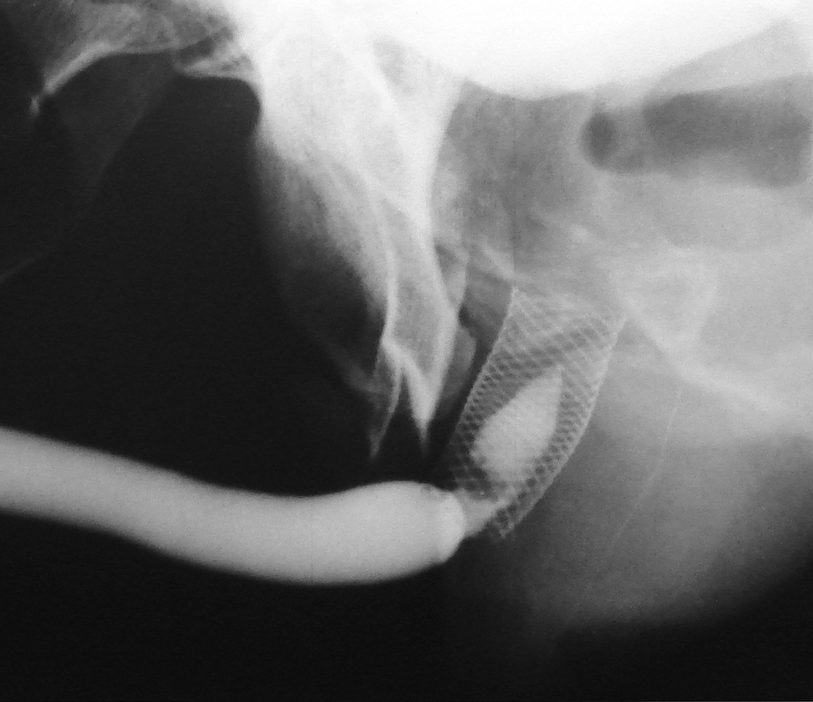

2.5 cm UroLume stent on bulbo-membranous urethra with hyperplastic overgrowth causing restenosis inside the prosthesis